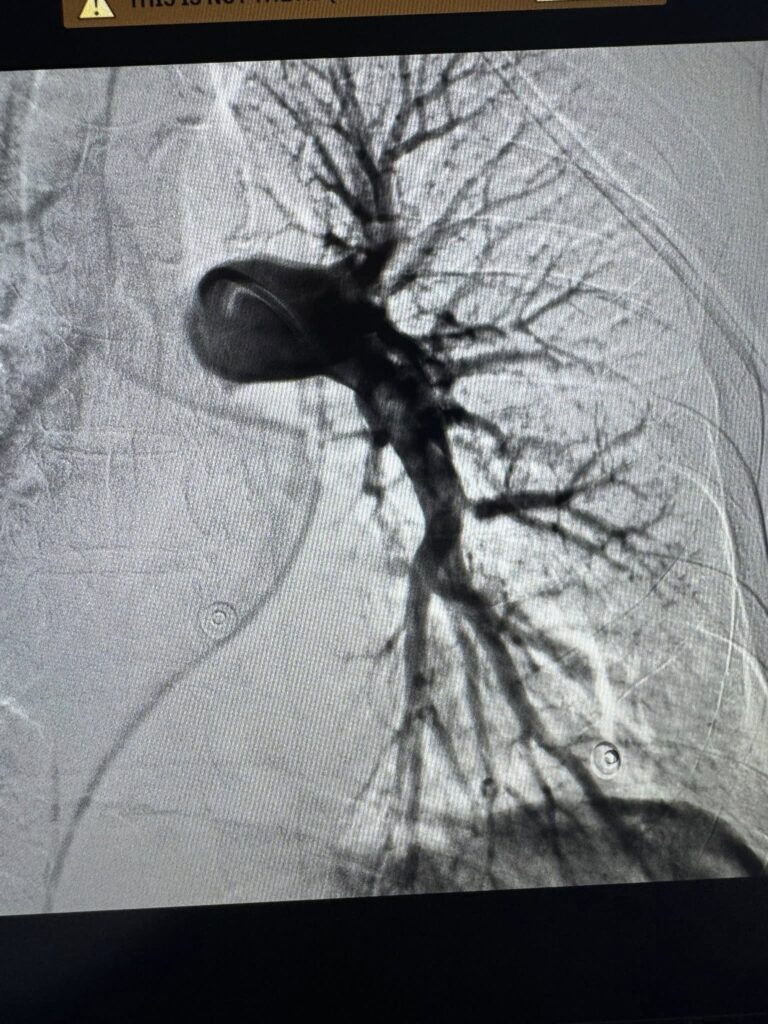

Вчора ввечері до нашої клініки потрапив чоловік із блискавичним розвитком тромбоемболії легеневої артерії — стану, який у багатьох випадках забирає життя за лічені хвилини. Другий – військовий, який лікувався в хірургічному відділенні з приводу мінно-вибухової травми та сьогодні отримав важку масивну тромбоемболію легеневої артерії.

Команда лікарів Першого територіального медичного об’єднання міста Львова прийняла рішення в обох випадках провести ендоваскулярну тромбаспірацію — сучасне, малоінвазивне втручання, що дозволяє механічно видалити тромб із легеневої артерії без відкритої операції. Саме цю методику освоїли нещодавно на конгресі інтервенційних радіологів в Барселоні!

Під рентгенконтролем через судини катетером ми дісталися тромбів й видалили їх спеціальною системою аспірації.